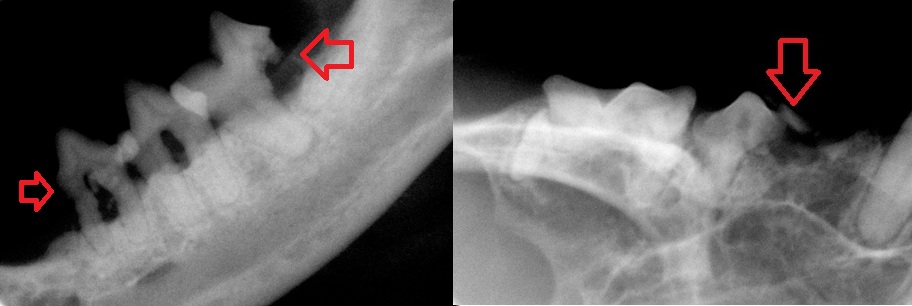

↑上の症例の歯の収集病巣

↑ほかの症例の歯の吸収病巣